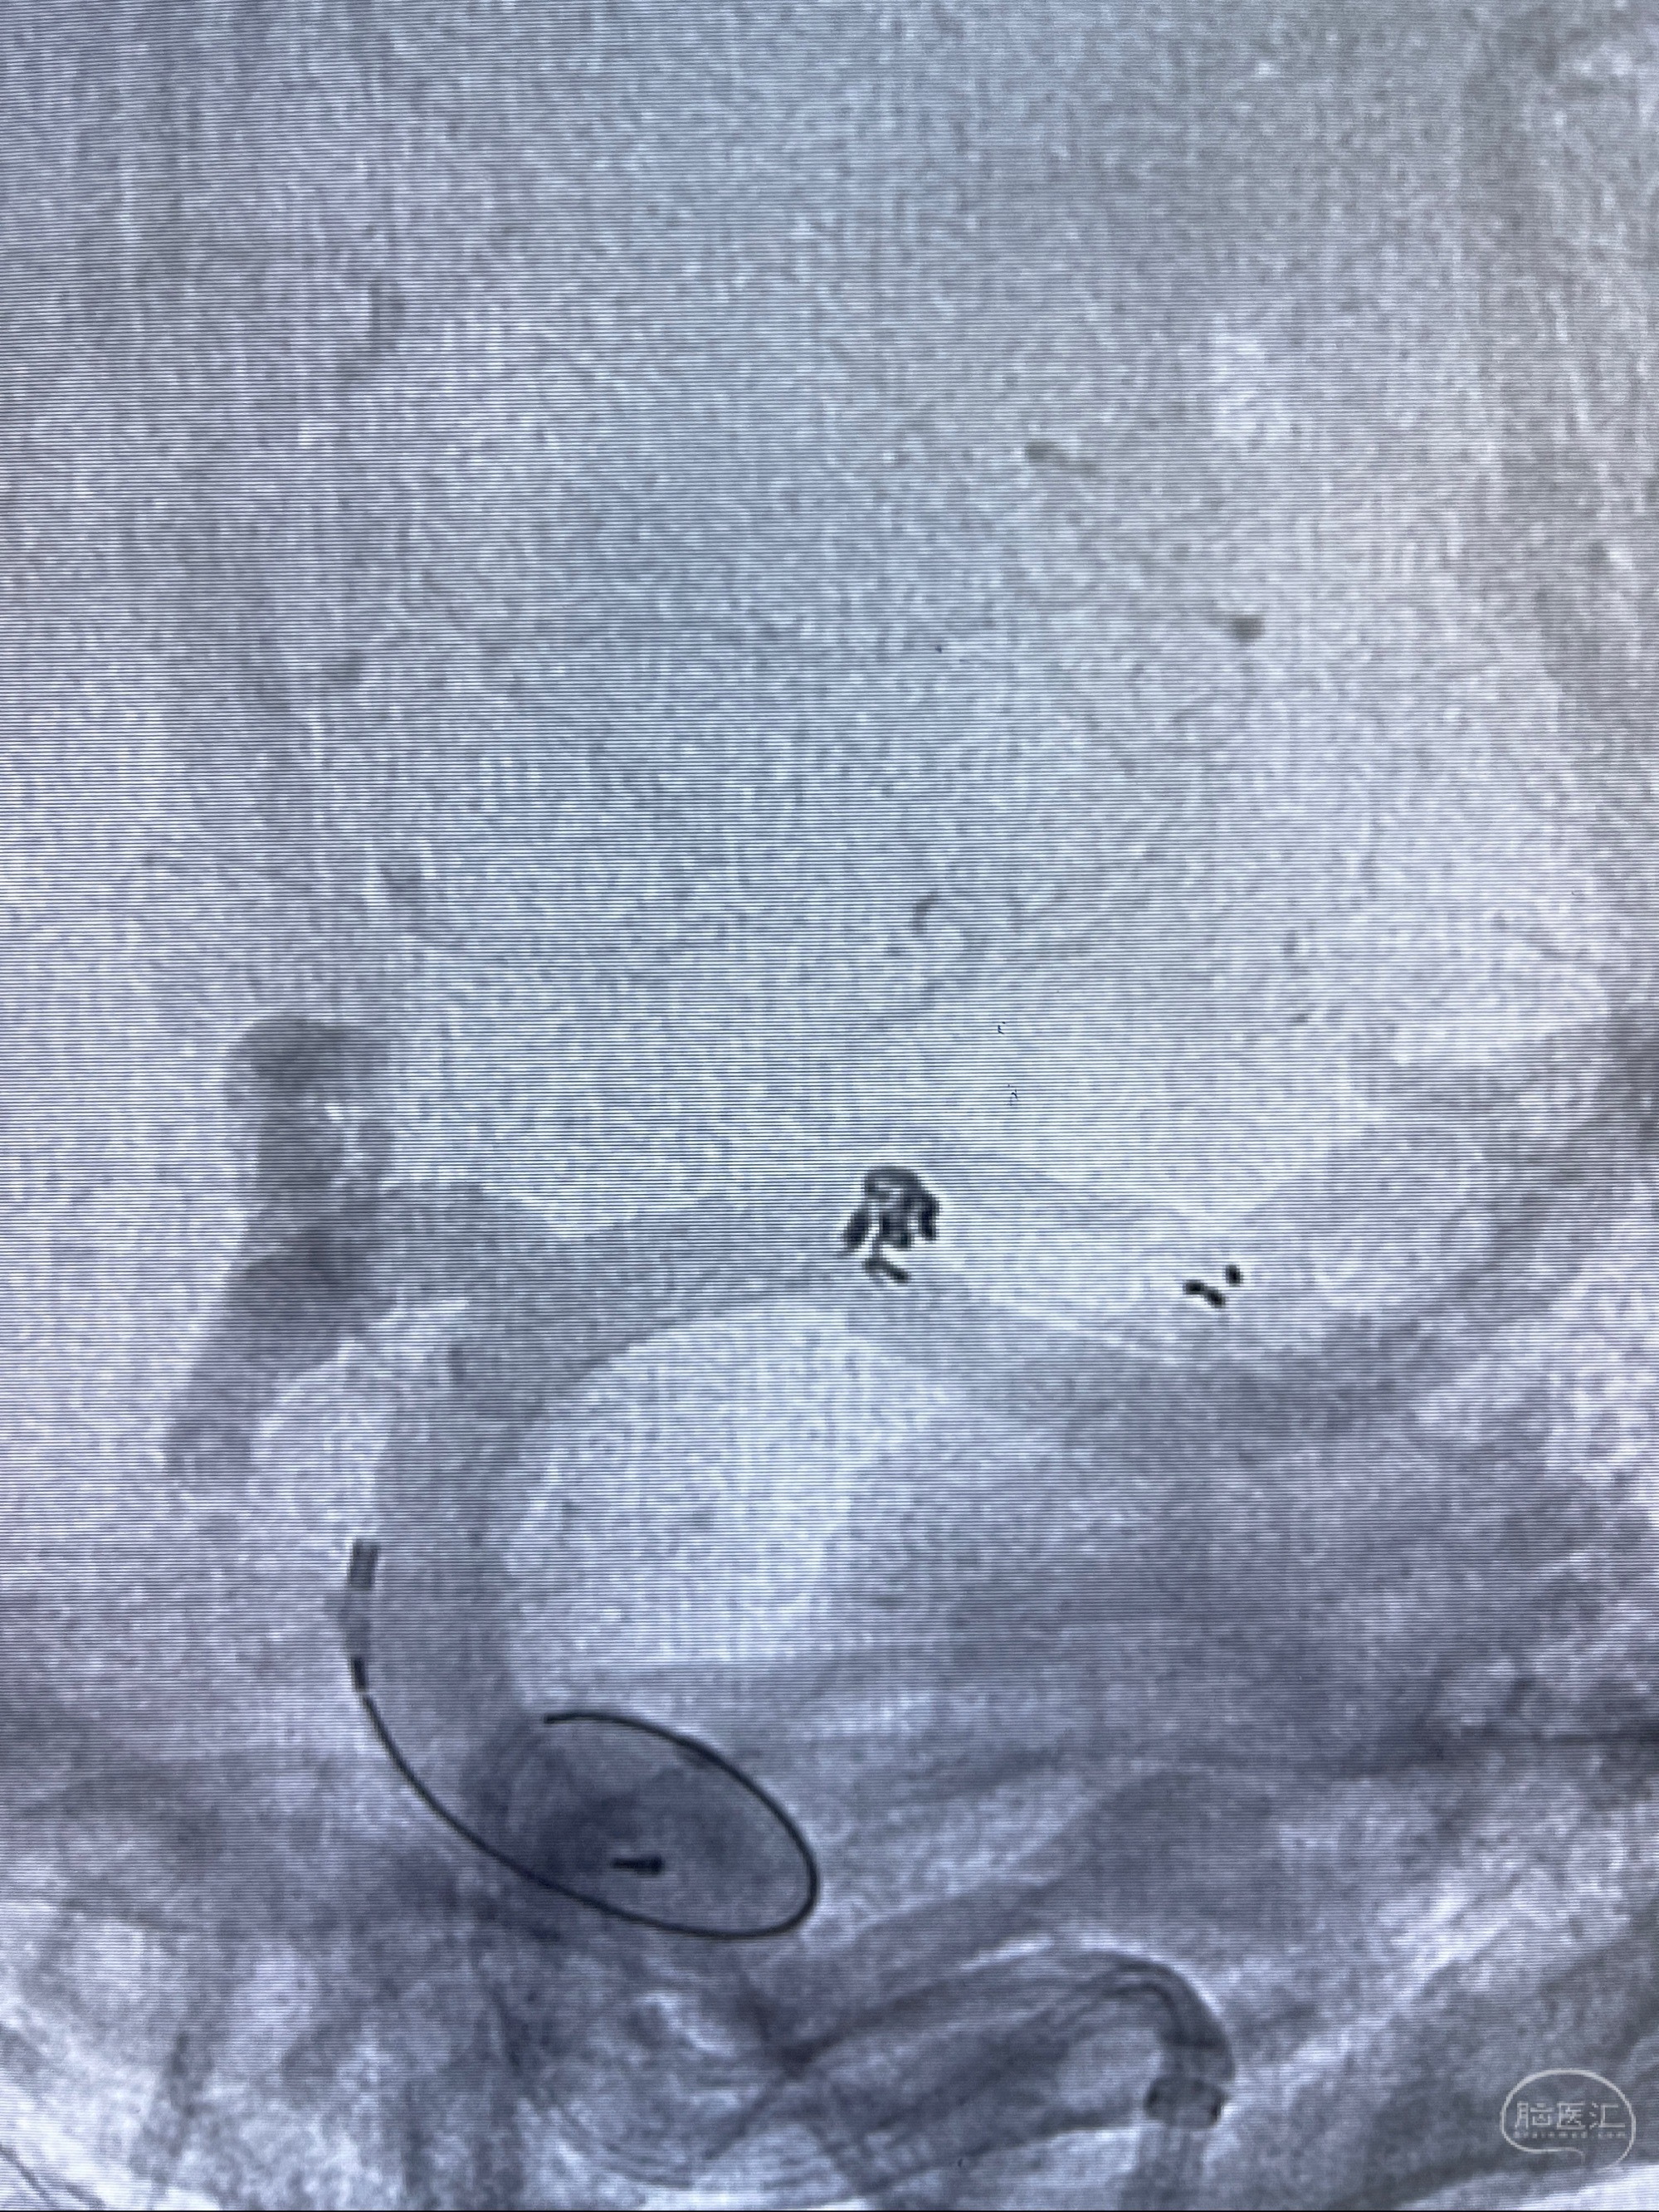

麻醉苏醒佳,遵嘱动作

术后即刻CT